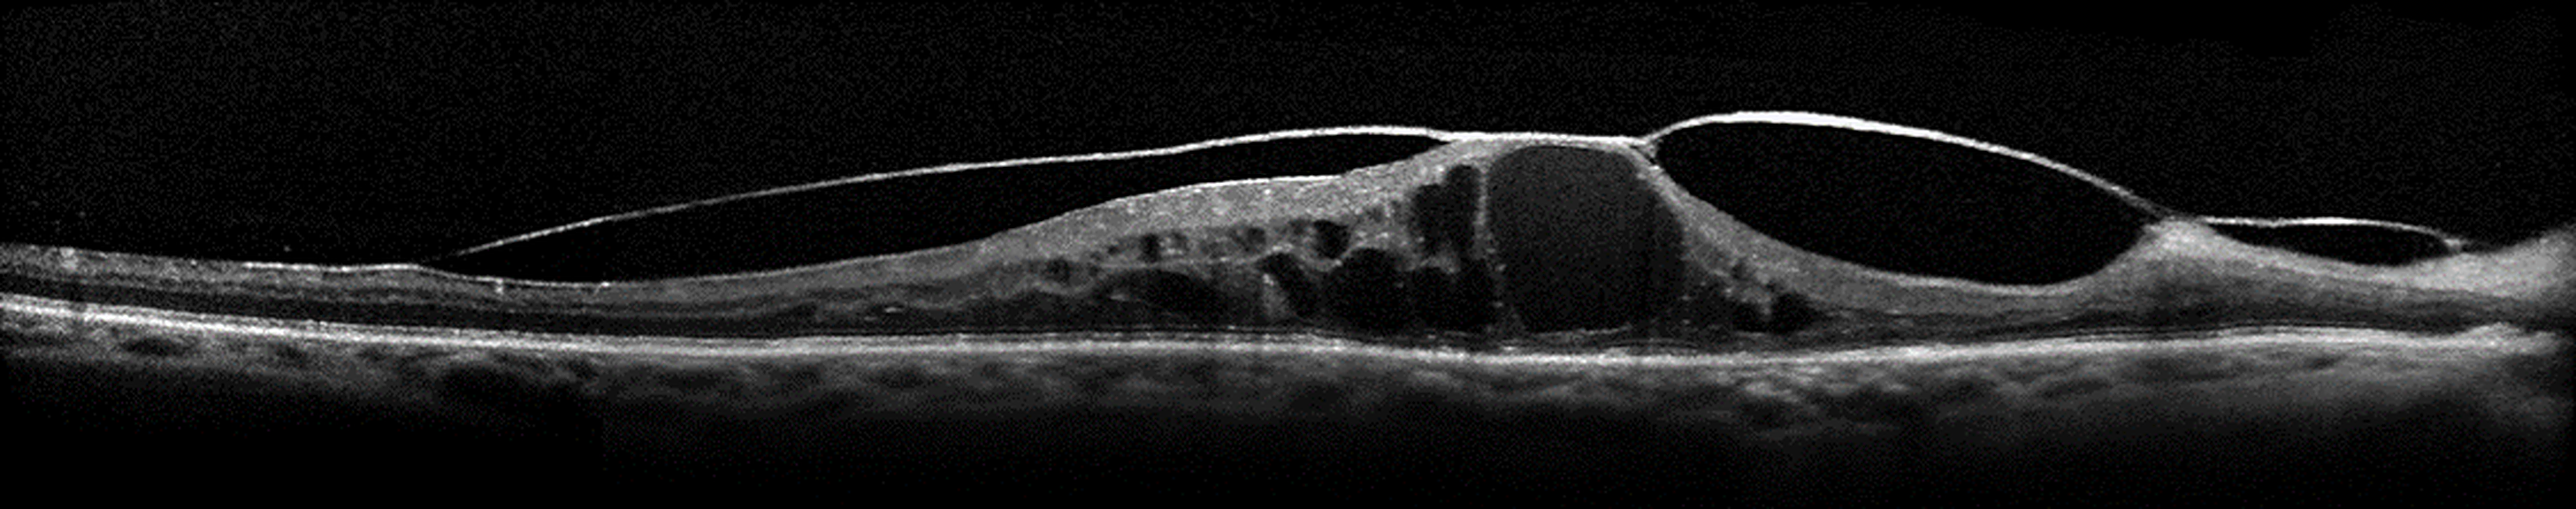

Indications chirurgicales dans la rétinopathie diabétique

La rétinopathie diabétique est une affection fréquente touchant une population jeune et active.

Dans ce contexte, il est nécessaire pour les ophtalmologistes de pouvoir identifier les différents signes cliniques afin d'assurer une bonne prise en charge du patient diabétique.

Identifier les indications chirurgicales

Rappeler les principes de chirurgie dans cette pathologie